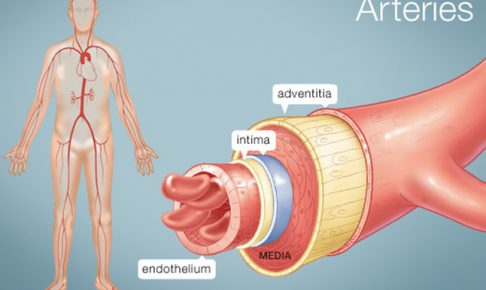

解剖学

解剖学

こんにちは!横浜本牧パーソナルトレーナー宮原崇です。 今日は天気も良く、本牧も多くの人で賑わっていました。 夕方に有隣堂の本店に行き、調べたいことがあったのですが、確定申告の書類整理のために断念しました。 本牧にもそのう…